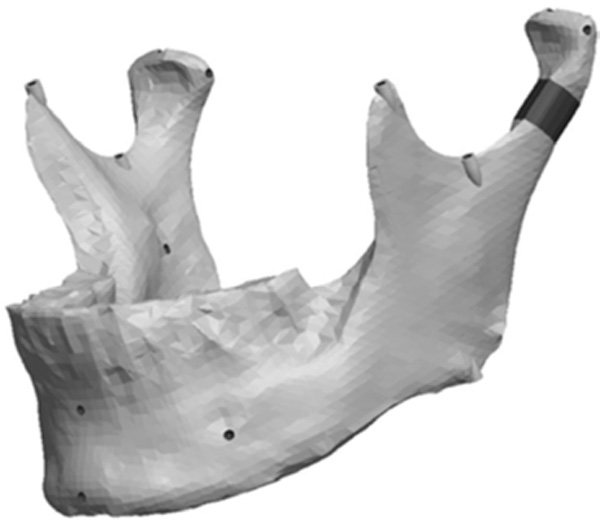

Fig. (8) depicts the location in the condylar neck for the sections made to generate the condyle asymmetries. From this section, vertical and complex asymmetries were constructed in the condylar region. The vertical manipulation created was to a maximum of 9mm asymmetry on 3mm increments and the complex condylar asymmetries were 9mm vertical and 6mm horizontal lateral asymmetry with 3mm vertical and 2mm lateral increments. Fig. (9) and Figure 10 represent images of models with vertical condylar asymmetry and models with the complex vertical and horizontal lateral condylar asymmetry respectively.

The Ramus section was located half way between the superior aspect of the condylar head and the depth of the antigonial notch. The location for the cut was determined by constructing a point half way between the most superior point on the condyle head (Cs) and the depth of the antigonial notch (Ag). A plane was selected perpendicular to the Cs-Ag line and plane MD which was used to guide the cut that penetrated through the neck of the condyle running parallel to the occlusal plane. Fig. (13) represents the location in the ramus of the mandible for the sections made to generate the ramus asymmetries. From this section, vertical and complex asymmetries were constructed in the ramal region. The vertical manipulation studied was to a maximum of 9mm asymmetry on 3mm increments and the complex ramal asymmetry was maximum of 9mm vertical with 3mm increments and 6mm horizontal lateral asymmetries with 2mm increments Fig. (14) and Fig. (15) represent images of models with the vertical ramal asymmetry and with the complex vertical and horizontal lateral ramal asymmetry respectively.